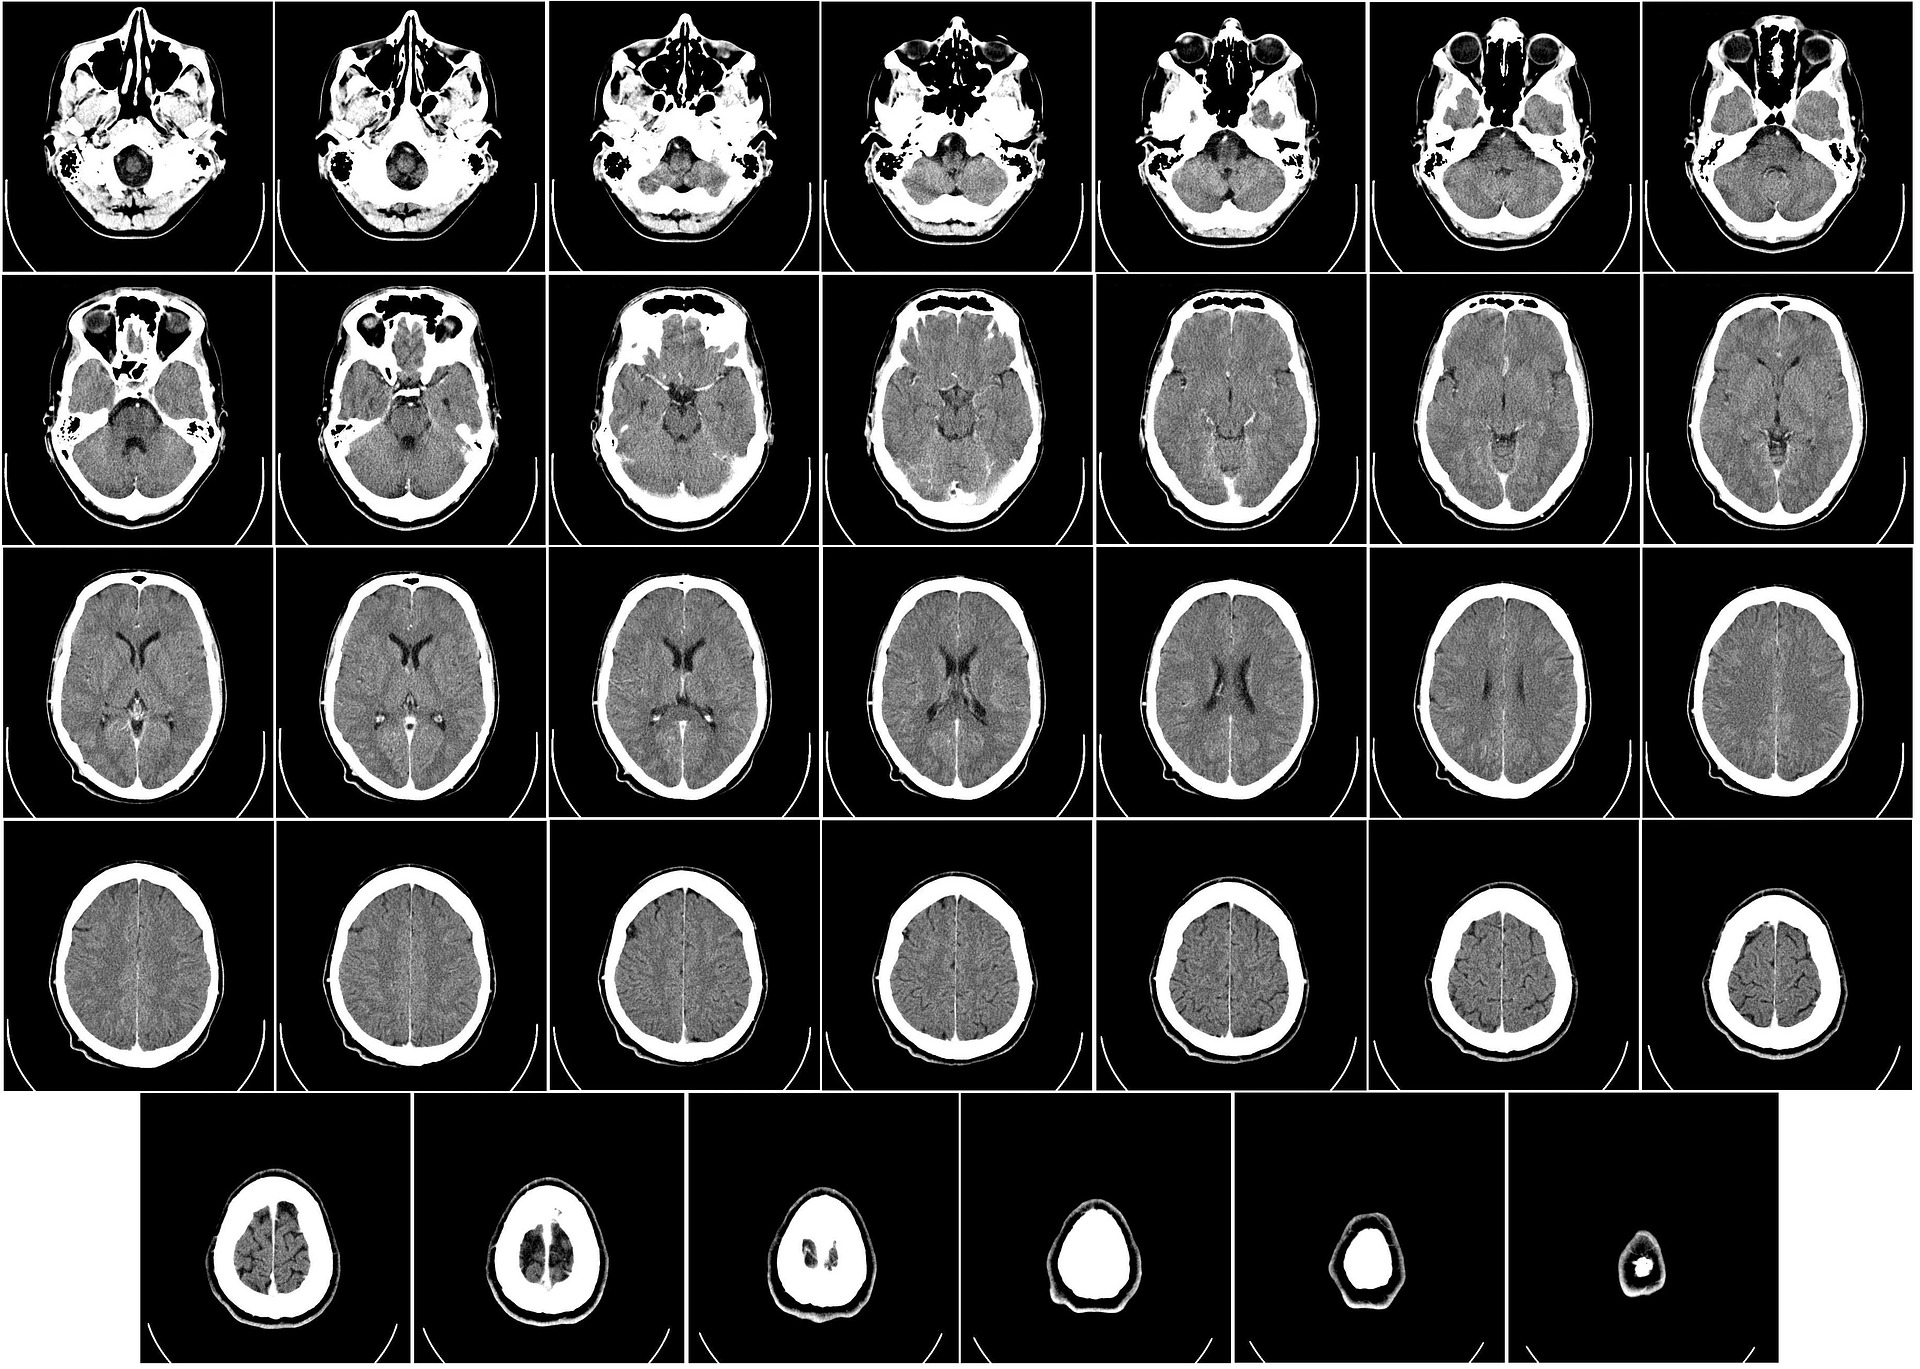

○뇌졸중이란? : 뇌경색과 뇌출혈을 함께 일컫는 말입니다.

뇌졸중은 뇌로 가는 혈류가 충분하지 않거나 순간적으로 너무 많아서 혈류가 끊기는 것이 원인이 되며, 뇌의 일부분에 혈액을 공급하고 있는 혈관이 막히거나(뇌경색) 터짐(뇌출혈)으로써 뇌가 손상되어 나타나는 신경학적 증상을 말하며, 우리나라에선 "중풍"이라는 말로도 불리고 있습니다.

○뇌출혈이란? : 뇌졸중에서 혈관의 터짐으로 발생하게 됩니다.

사람의 두개 내의 출혈이 발생되어 생기게 되는 모든 변화를 말하며, 출혈성 뇌졸중이라고 합니다. 뇌출혈은 크게 외상에 의한 출혈과 자발성 출혈로 구분합니다.

● 뇌혈관이 막혀 발생하는 뇌경색 : 일과허혈발작, 대혈관질환에 의한 뇌경색, 소혈관질환 및 열공 뇌경색, 심장질환에 의한 심인성 뇌경색 등으로 분류됩니다.

●출혈성 뇌졸중(뇌출혈) : 뇌내출혈 및 두개내출혈, 뇌실내출혈, 거미막 밑 출혈, 경막 외출혈, 경막하출혈로 분류됩니다.